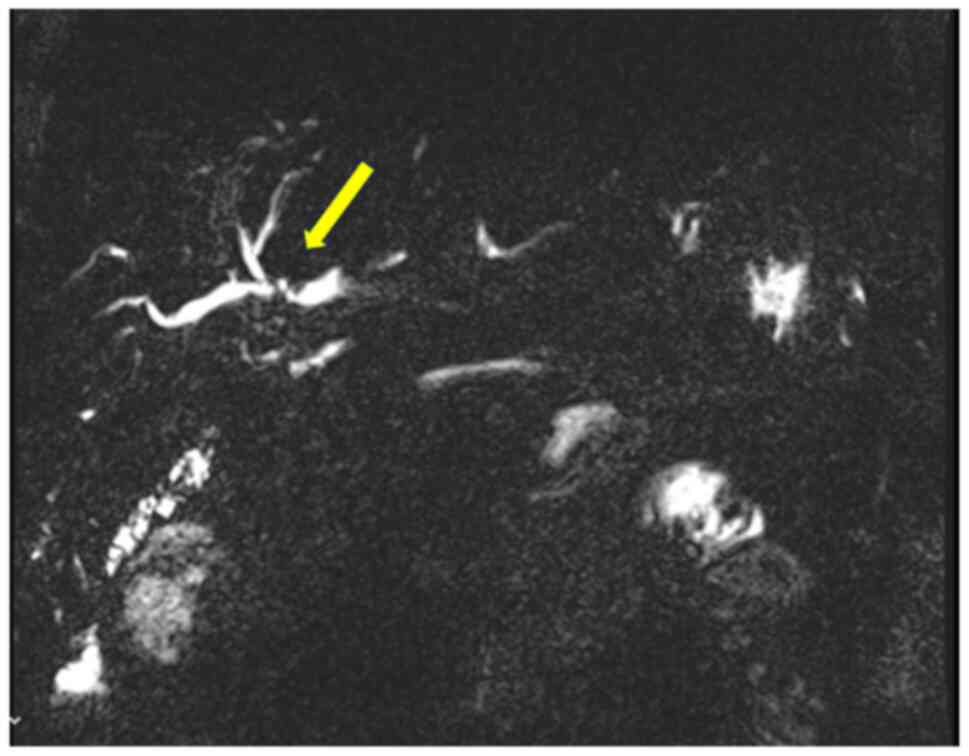

In March 2021, a new hilar stricture was identified in the liver graft. Magnetic resonance cholangiopancreatography and biopsy revealed features of ischemic cholangiopathy, possibly from prior rejection, although recurrent PSC could not be excluded (Fig. 6). FDG-PET revealed no evidence of disease recurrence. A suspected anastomotic stricture at the hepaticojejunostomy was treated with balloon dilation via percutaneous transhepatic cholangiography, leading to the resolution of liver function abnormalities. The ileostomy was reversed in March, 2022.

MRCP illustrating a new hilar

stricture at the hepaticojejunostomy (yellow arrow), consistent

with ischemic cholangiopathy in the liver graft (March, 2021). This

was treated with balloon dilation.

Figure 6

MRCP illustrating a new hilar stricture at the hepaticojejunostomy (yellow arrow), consistent with ischemic cholangiopathy in the liver graft (March, 2021). This was treated with balloon dilation.